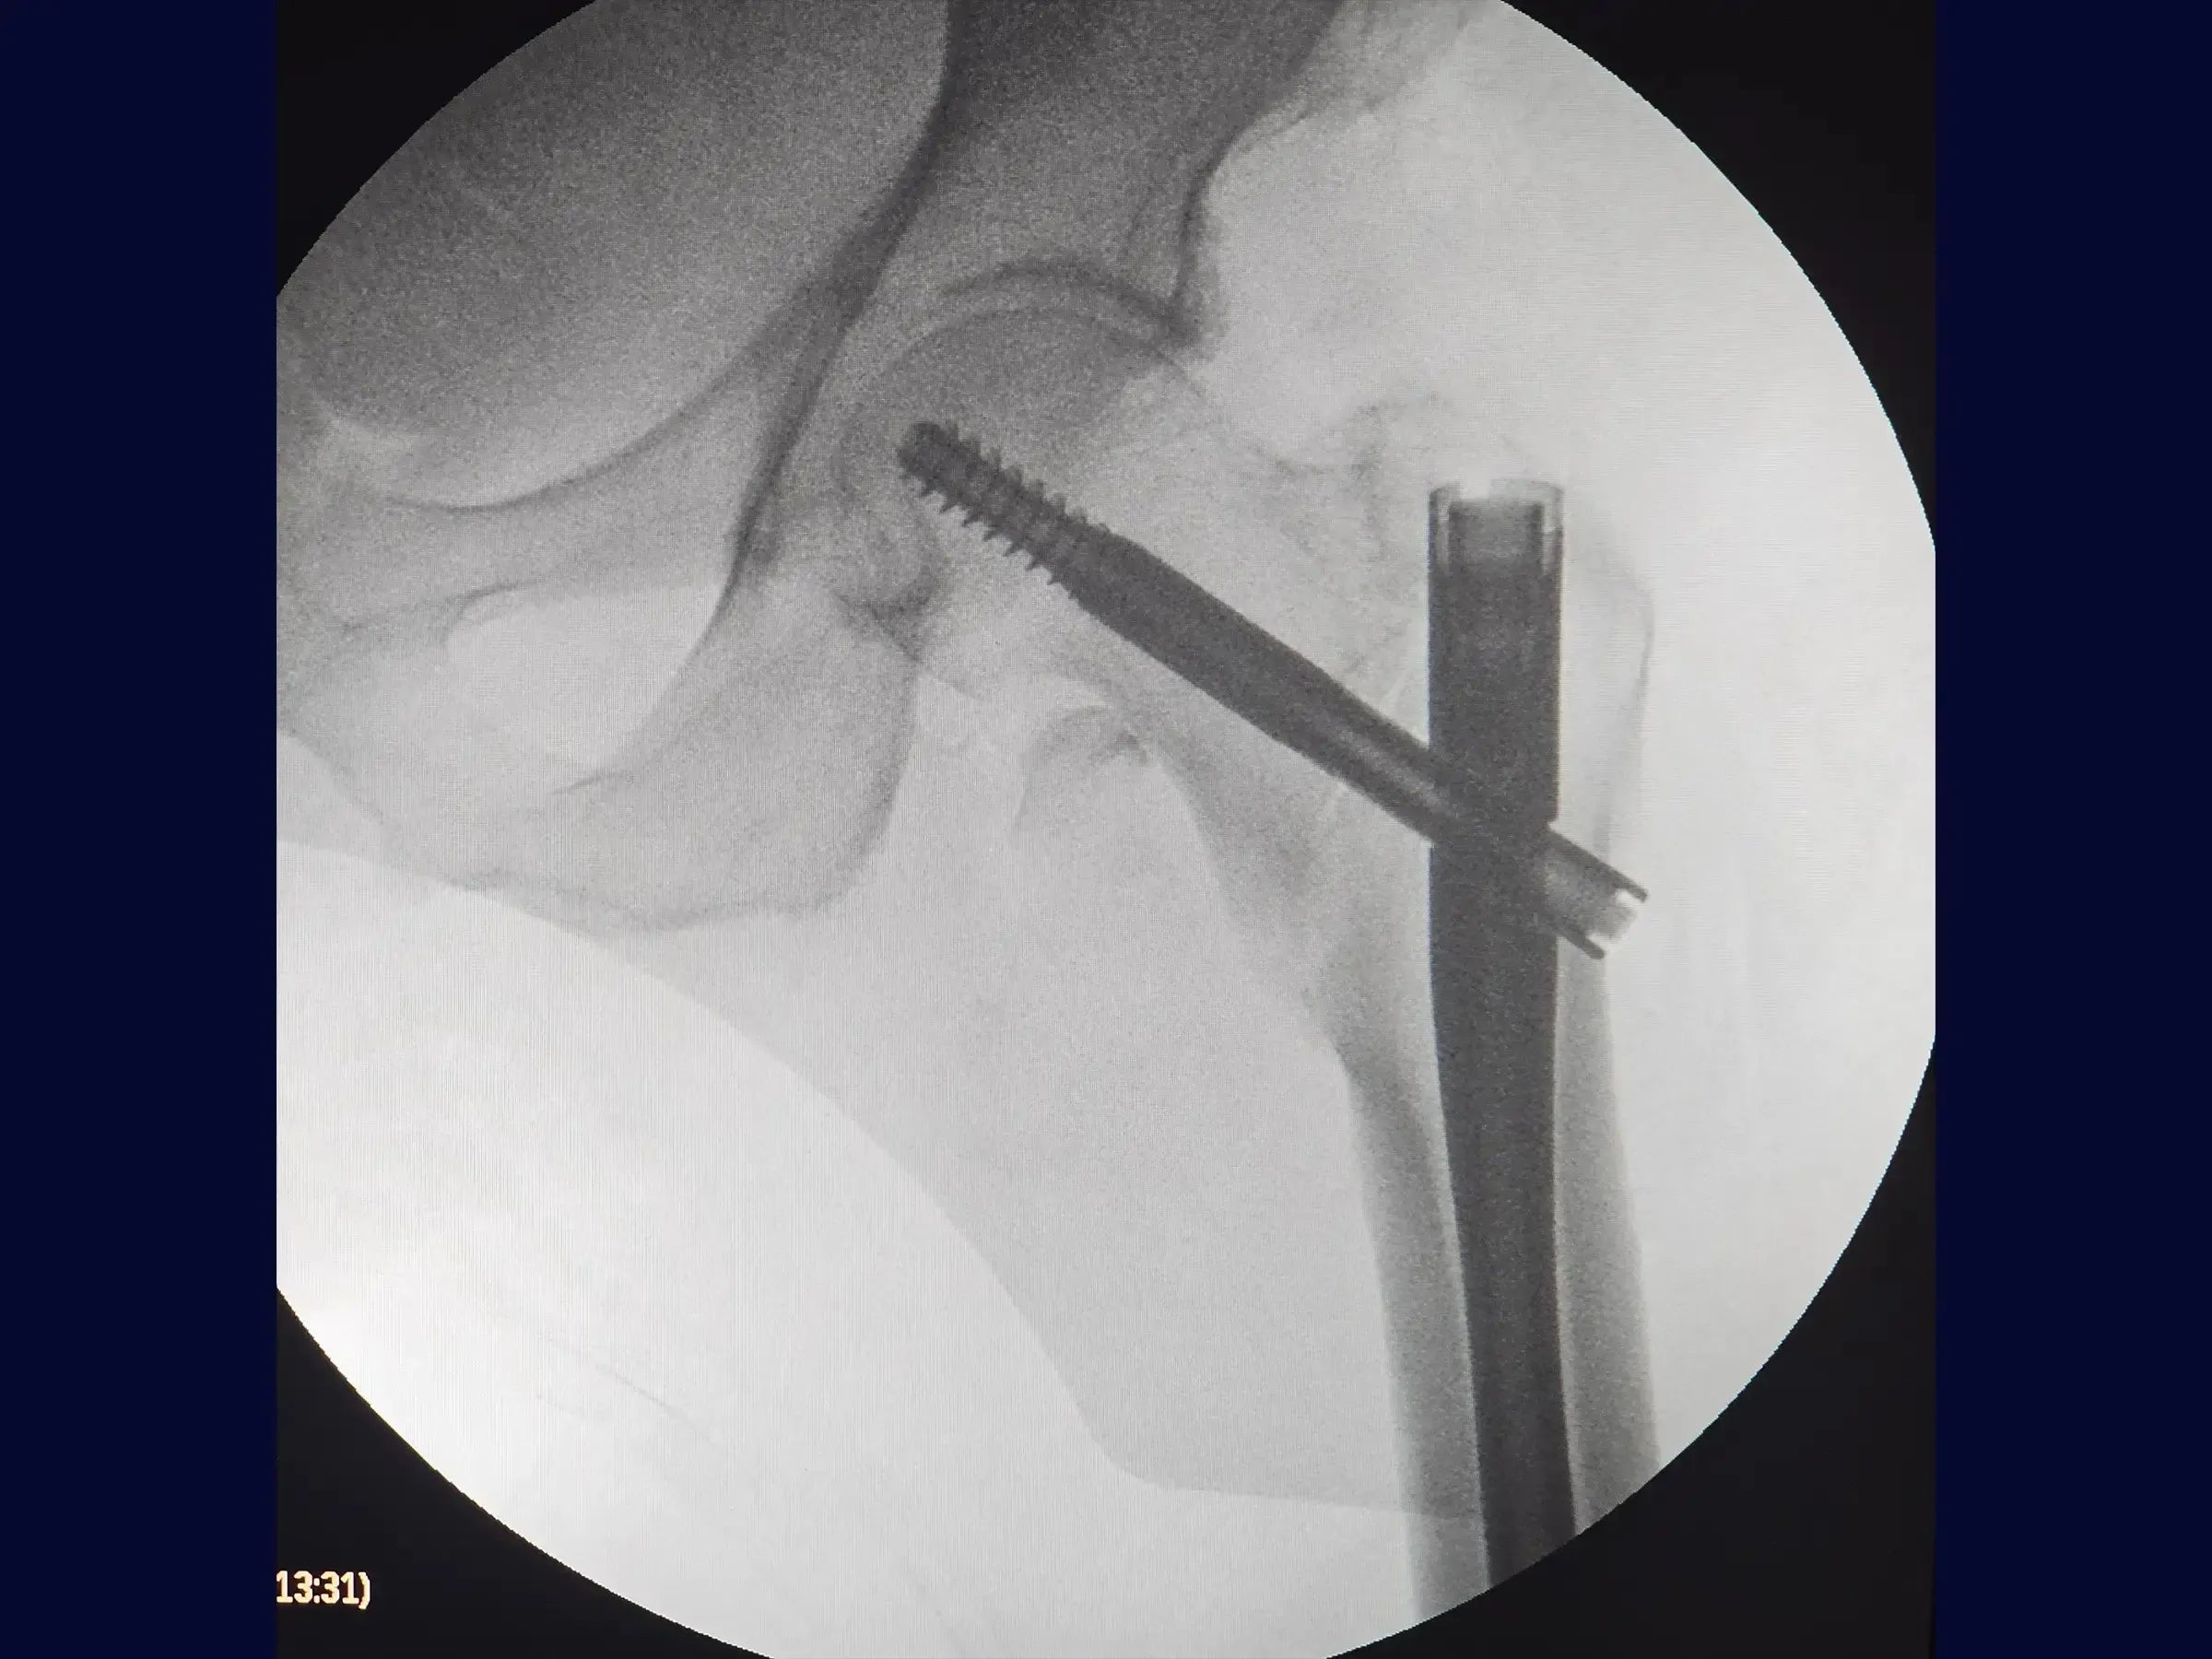

- Clavo Intramedular Corto: Abordaje sistemático para la inserción del clavo y la extracción de la guía, considerando los desafíos de la impactación y el desplazamiento en valgo.

- Maniobra de reducción en balancín: Demostración de la técnica de reducción para fragmentos proximales valgos o impactados, incluida la creación de un miniportal seguro y la aplicación de la palanca para obtener y mantener la reducción anatómica con una manipulación mínima.

- Fijación Definitiva: Secuencia de introducción del alambre guía y tornillo deslizante, posicionamiento estratégico del tornillo de bloqueo (con ajuste para pistoneo) e inserción del tornillo de bloqueo distal, asegurando la estabilidad.

- Apertura segura del canal medular: técnica para utilizar la guía/protector de tejidos blandos, dirigiéndolo medialmente para proteger la corteza lateral del fémur durante el escariado.